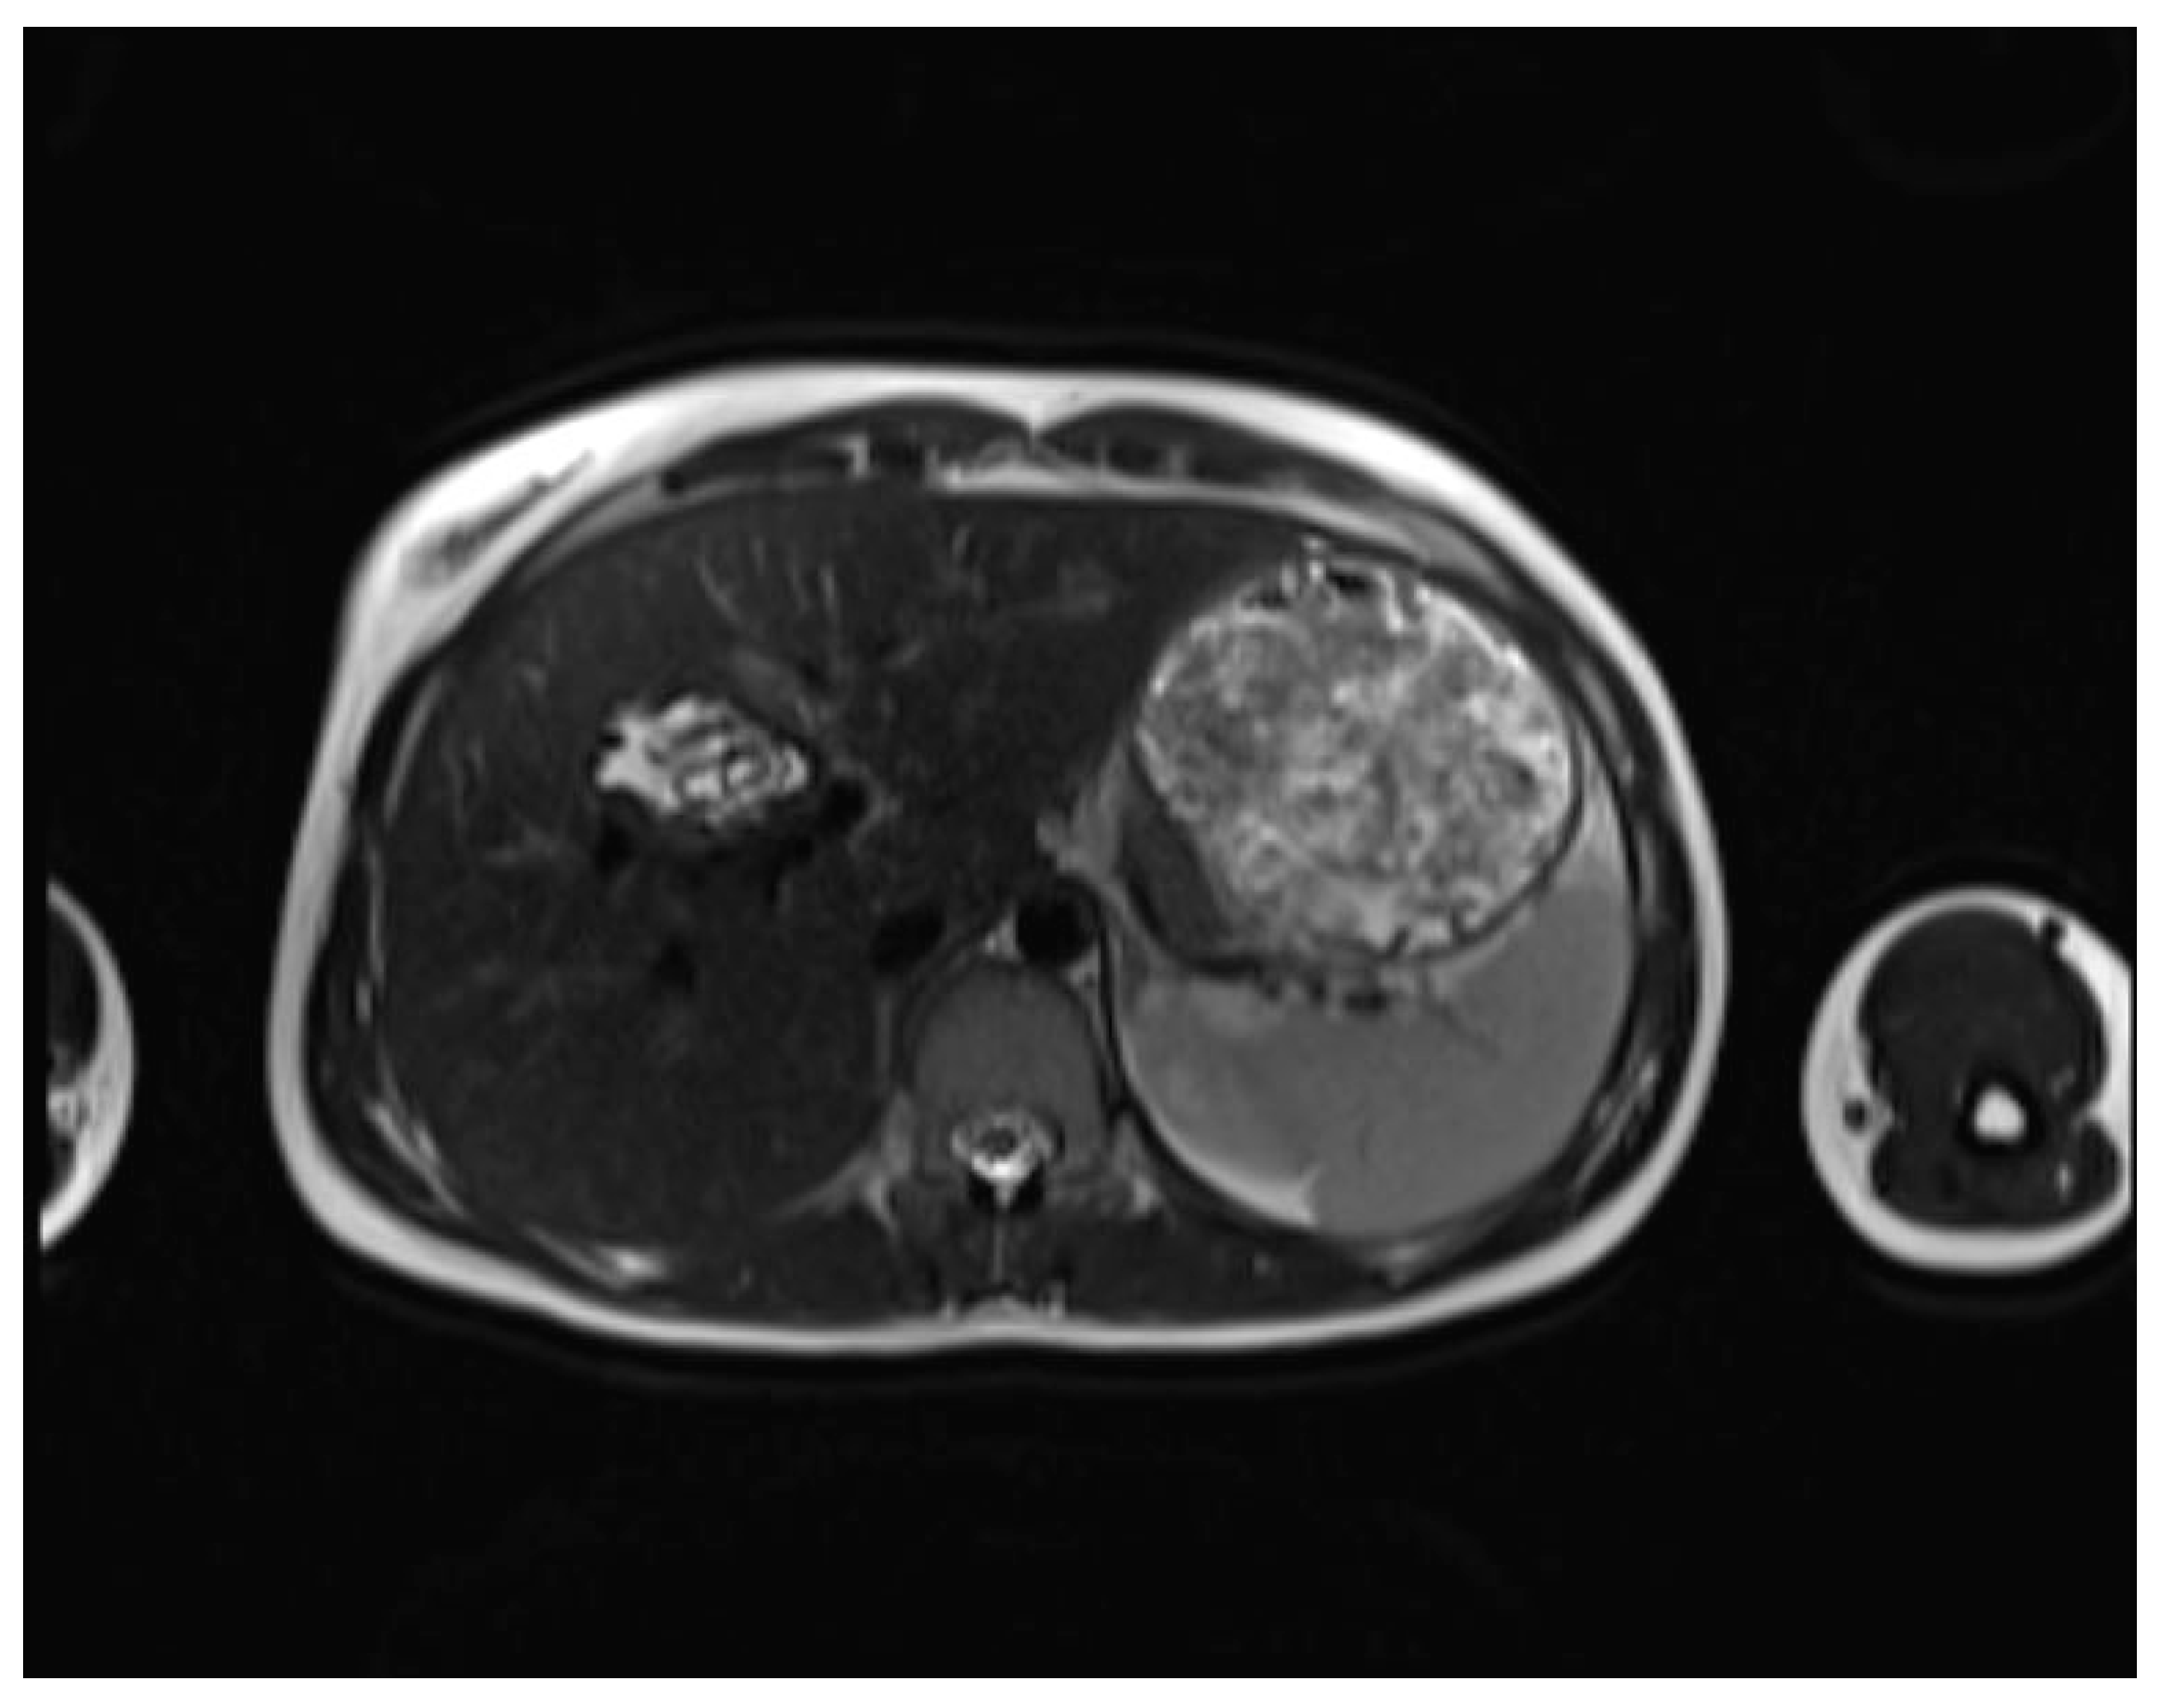

| CE1 (Simple cyst) | Well-defined, unilocular cyst with a peripheral capsule, hypointense on T2WI, possible rim sign. Hyperintense hydatid matrix on DWI and ADC. | Unilocular anechoic cyst with possible rim sign and internal echoes (hydatid sand, snowflake sign) seen after repositioning. |

| CE2 (Cyst with daughter cysts and matrix) | Multicystic mass with septa (wheel-spoke pattern), daughter cysts are hypointense or isointense compared to the mother cyst on both T1WI and T2WI. | Well-defined cyst with multiple internal septations and daughter cysts, described as honeycomb or rosette appearance. |

| CE3A (Transitional) | Detachment of laminated membranes, with a floating water lily sign or serpent sign. Daughter cysts may be visible in the matrix. | Internal floating membranes or detached laminated membranes (water lily sign). |

| CE3B (Transitional; daughter cysts within solid matrix) | Solid matrix with visible daughter cysts; signal intensity varies depending on the proteinaceous content of the cyst. | Similar to CE3A, but daughter cysts are present within a solid matrix, often with calcification. |

| CE4 (Complicated or inactive cyst) | Heterogeneous mass with hypointense and hyperintense areas, often partially or completely calcified. Inactive stage. May show signs of complication like rupture (biliary communication) or infection. | Cyst with heterogeneous hypoechoic and hyperechoic contents, resembling a ball of wool; absence of daughter cysts. |